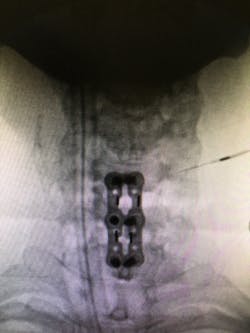

After viewing the films, he agreed that an anterior discectomy/laminectomy and fusion of Cervical 5-7 with a bone graft was the best surgical procedure. He outlined in detail what the procedure included from beginning to end, and he expressed his confidence in actually performing the procedure. He left the decision up to me, and I quickly made the choice to schedule the surgery and try what may be my last resort.

I am three weeks post-surgery, and I have no headache or neck pain, nor am I taking any medication. It will be six months to fully identify if the surgery is a complete success. At this point, I am hopeful.